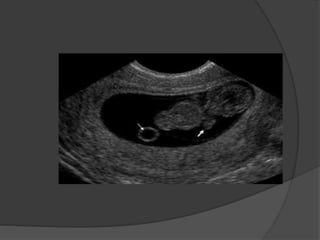

 Multiple pregnancies and types of twinning depends on

the number of zygotes and timing of division and they are

:

1- Dizygotic twins : two fertilized ova and they are all

dichorionic , diamniotic

2- Monozygotic twins : the amnionicity and chorionicity

depends by the time of zygote division

- Before 3rd day post conception : diamniotic, dichorionic

- 4th-8th day post conception : monochorionic , diamniotic

- Cleavage of the inner cell mass of blastocyst after 8th day

post conception : monochorionic, monoamniotic.

- Incomplete cleavage of embryonic disc after 13th day post

conception : conjoined twins

Monoamniotic monochorionic

twins

Multiple Pregnancy  Multiplepregnancies and types of twinning depends on the number of zygotes and timing of division and they are : 1- Dizygotic twins : two fertilized ova and they are all dichorionic , diamniotic 2- Monozygotic twins : the amnionicity and chorionicity depends by the time of zygote division - Before 3rd day post conception : diamniotic, dichorionic - 4th-8th day post conception : monochorionic , diamniotic - Cleavage of the inner cell mass of blastocyst after 8th day post conception : monochorionic, monoamniotic. - Incomplete cleavage of embryonic disc after 13th day post conception : conjoined twins